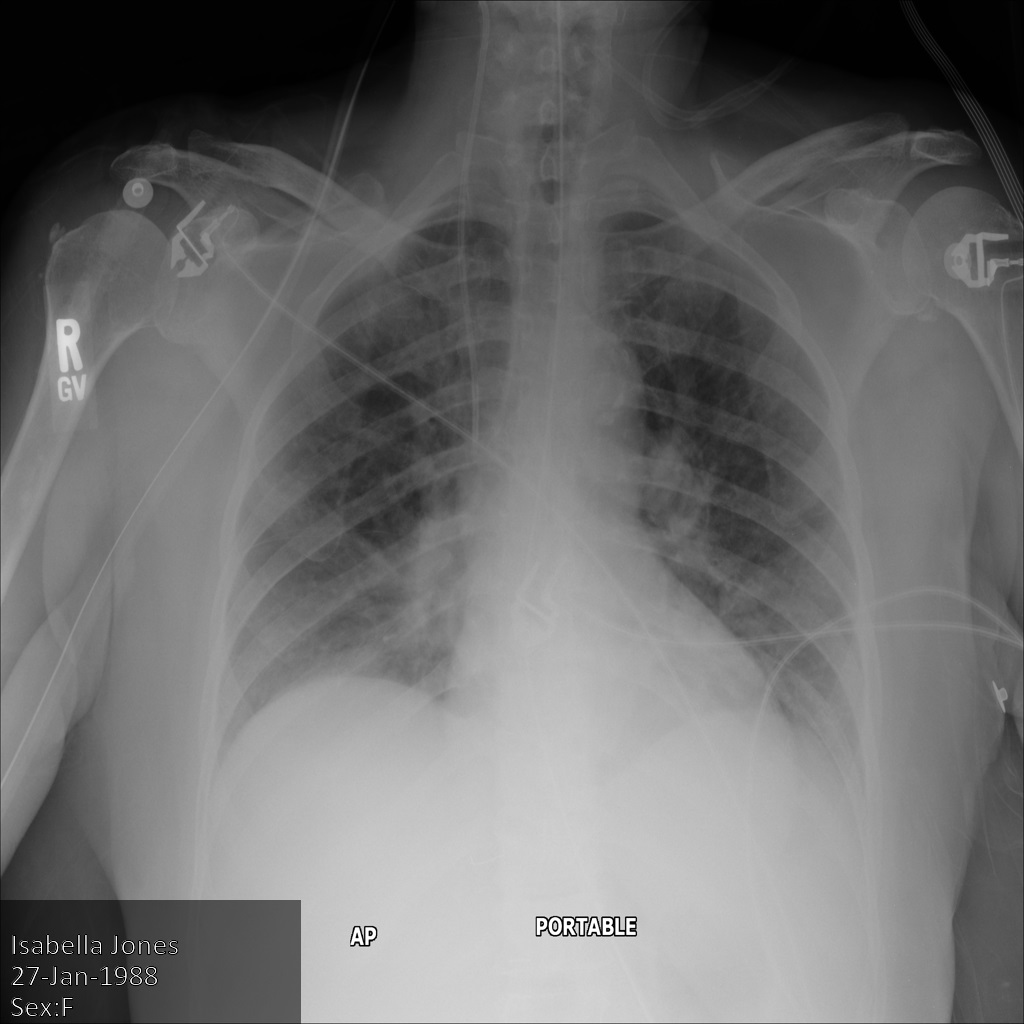

다음 이미지는 환자의 수정되지 않은 x-레이를 보여줍니다.

REDACT_SENSITIVE_TEXT 옵션을 사용하여 Cloud Healthcare API에 이미지를 제출하면 이미지가 다음과 같이 표시됩니다.

다음과 같은 상황을 확인할 수 있습니다.

- 이미지 왼쪽 하단의

PERSON_NAME이 수정되었습니다. - 이미지 왼쪽 하단의

DATE이 수정되었습니다.

기본 DICOM infoType에 따라 민감한 텍스트로 간주되지 않으므로 환자 성별이 수정되지 않았습니다.